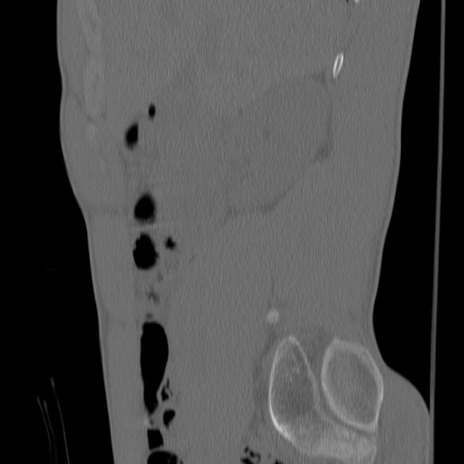

症例3 腰椎CT(矢状断像)

腰椎CT

冠状断像